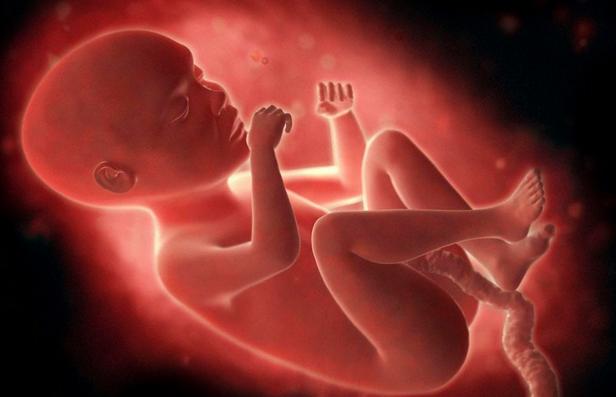

怀孕 胎儿

怀孕是件幸福的事情,欣喜之余,让粑粑麻麻最好奇的就是胎儿的性别,其实,男宝女宝都是粑粑麻麻的心肝宝贝,想知道宝宝的性别,就是为了准备东西,迎接宝贝的到来

民俗有很多方法鉴定胎儿性别,但是那都是几率,没有什么科学依据,要坚定胎儿性别,最好还是相信科学,有什么方法可以鉴定胎儿性别呢?